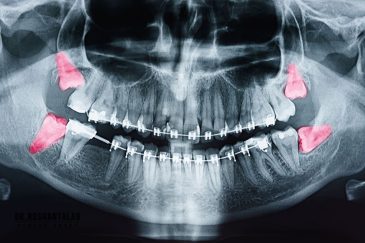

🔸کاشت ایمپلنت فلپ لس یا بدون جراحی و بدون بخیه زیر سه دقیقه

🔸 ایمپلنت دیجیتال و ساخت روکش دیجیتال

🔸جراحی پیشرفته نظیر سینوس لیفت